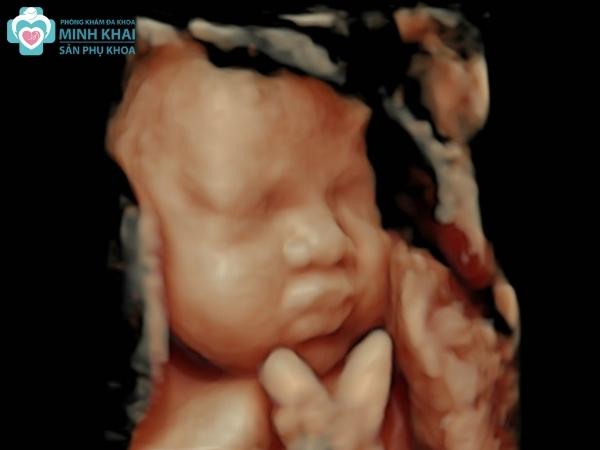

Hình ảnh siêu âm 4D

Hình ảnh siêu âm 4D thể hiện qua ảnh động các chuyển động liên tục của bé con ngay trong thời gian thực khi siêu âm. Thay vì ảnh đen trắng, siêu âm màu 4D cho những hình ảnh có màu sắc với độ phân giải cao và vô cùng chân thực, sắc nét hiển thị rõ trên màn hình. Thêm vào đó, hình ảnh siêu âm 4D còn được máy xử lý tự động cho phép người xem có thể chọn đa dạng các chiều mặt cắt, chế độ xem khác nhau.

Nó có thể chụp lại đầy đủ cấu tạo các bộ phận cơ thể cũng như tái hiện lại các cử chỉ của thai nhi như đạp chân, múa tay, cười,... Chi tiết hơn nữa, kỹ thuật 4D còn giúp quan sát được cấu trúc bộ xương cũng như đa chiều mặt cắt, siêu âm hệ thần kinh, não và tim.

Khi theo dõi hình ảnh siêu âm 4D, ba mẹ còn quan sát được kỹ và chi tiết nhất về đường nét khuôn mặt, giới tính cũng như cấu tạo các bộ phận cơ thể của con. Đây chính là niềm vui được ngắm nhìn từ trong thai kỳ đến lúc con sắp chào đời mà mẹ bầu nào cũng mong muốn.